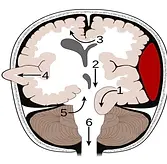

This eight year old boy complains of headache, lasting for last 3 months. No history of trauma. CNS exam including fundus was normal. Locallized tenderness noticed on the parietal side. No swelling. CT skull is enclosed

1. Radiological finding

2. Probable clinical dx?

3. Pathophysiology?

4. Specific Microscopic (EM) findings